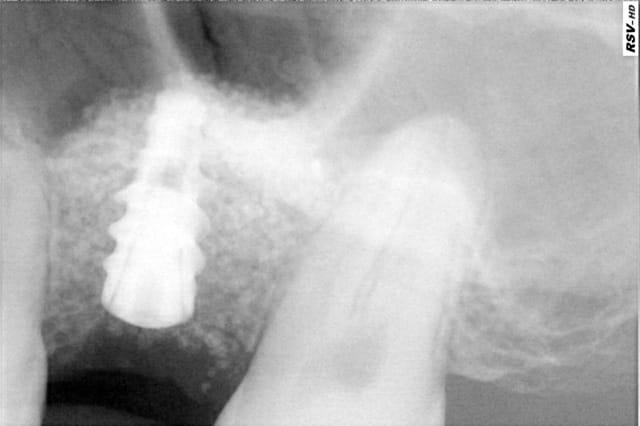

> avant d'envoyer le patient passer son cone-beam je n'étais pas convaincu que il

> y avait un kyste. comme quoi!

Sur la retro, on voit bien un manque de densité...

Je trouve ton 4 mm un peu petit...vu le manque d'os et le comblememt assez important...

J'aurais placer un 4.5 mm , mais bon.

en fait, quand j'ai commencé à forer avec le 2.4, je me suis vite aperçu que l'ancrage serait très faible (environ 5mm) puis en forant avec le foret 3.4, le diamètre s'élargissant, j'ai eu un doute.

il faut savoir qu'avec les nouveaux implant PX il faut sous-forer.;

-pour un implant diamètre 3.4 on fore à 2.4

-pour un implant diamètre 4 on fore à 3.4

en ayant foré à 3.4, j'avais donc deux choix possible:

soit poser un AXIOM REG de diamètre 3.4mm

soit poser un AXIOM PX de diamètre 4 mm.

c'est sympa d'ailleurs d'avoir le choix pour un même forage

j'ai donc commencé à poser le PX de diam 4 en me disant que si je ne le sentais pas, je laisserai l'implant en nourrice après avoir fait un lambeau pédiculé de recouvrement sur le site d'intervention.

à ma grande surprise,l'implant à bloqué à 50n.cm avant d'être à la bonne profondeur. j'ai donc fini à la clée et du coup... fais la mise en esthétique.

résultat, cet implant est top pour les MCI!